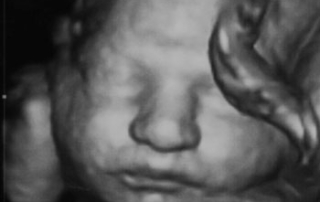

ייעוץ במומים

מה עושים כשמתגלה מום בעובר? התייעצי עם מומחה כדי לקבל את המידע הנכון והרלוונטי לפני קבלת החלטה בלתי הפיכה.